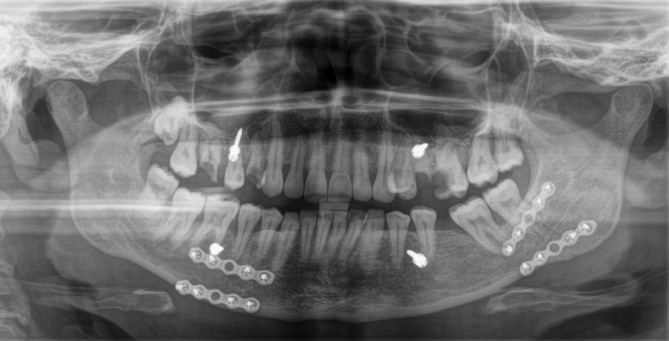

Methods: In this retrospective two-center cohort study, patients who underwent surgical treatment for mandibular angle fractures via a transoral approach using either 1-plate or 2-plate fixation over a 10-year period were included. Clinic A exclusively performed 1-plate fixation, while clinic B used 2-plate fixation. Demographic, clinical, radiological, and treatment data were analysed. Multivariable analyses were conducted to identify predictors of postoperative complications and secondary osteosynthesis.

Results: A total of 253 patients with 264 mandibular angle fractures were included. Violence was the most common mechanism of injury (n = 131; 49.6%). Postoperative complications occurred in 34.6% of the cases at clinic A and 26.8% at clinic B (p < 0.0001). Secondary osteosynthesis was required in 9.4% at clinic A and 7.6% of the cases at clinic B, respectively (p = 0.6547). Multinomial regression analysis identified smoking, diabetes mellitus, patient noncompliance, left-sided mandibular angle fractures, presence of a third molar (M3), partial M3 eruption, vertical depth A of M3 and horizontal impaction class II (Pell and Gregory) as significant predictors of postoperative complications. Logistic regression analysis identified smoking, diabetes mellitus, patient noncompliance, left mandibular angle fractures, mandibular angle und body fractures and presence of third molars as significant predictors of secondary osteosynthesis. As patient age there is an increased tendency for wound infection and plate/screw loosening (p = 0.06). A longer interval between trauma and surgery was associated with a higher risk of postoperative occlusal disturbances (p = 0.06). Patients with a longer duration of postoperative IMF were significantly associated with a higher rate of wound infection and secondary osteosynthesis (p < 0.05).

Conclusions: Both 1-plate and 2-plate fixation techniques demonstrated acceptable outcomes. Single-plate fixation offers sufficient stability for most mandibular angle fractures with fewer complications, supporting its use in uncomplicated cases. Double-plate fixation may be reserved for complex cases. Higher complication rates were associated with patient-related and anatomical risk factors. Individualized treatment and further prospective studies are needed to refine surgical strategies.